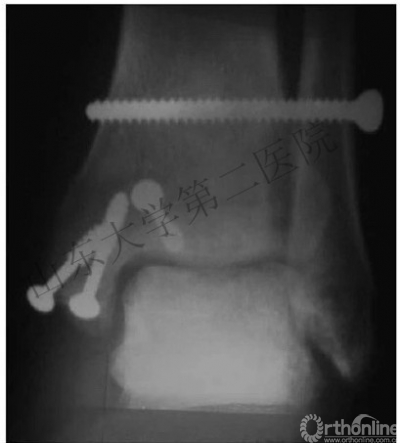

2.下胫腓联合的治疗

(2)下胫腓联合以两枚下胫腓螺钉固定。

※下胫腓螺钉位置:

*胫距关节面近端2-4cm,并且平行于关节面。

*水平面上从后向前有30°夹角。

*2枚螺钉or1枚?

有高位腓骨骨折时,打2枚螺钉;其他的打1枚螺钉。

4.下胫腓联合需要用两枚下胫腓螺钉固定,除非可以确定下胫腓联合是否稳定。

5.在固定下胫腓联合的时候,需要恢复腓骨长度和旋转,将足放于中立位。